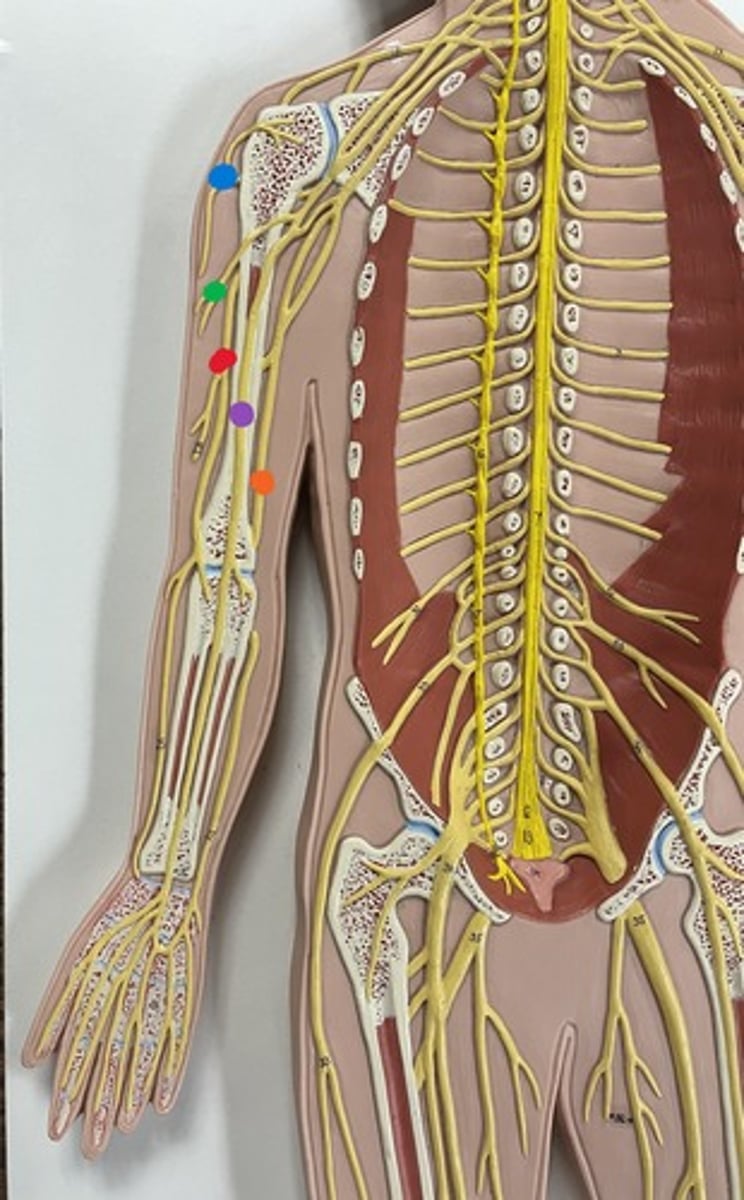

Brachial plexus

Axillary nerve

blue

Musculocutaneous nerve

green

Median nerve

purple

Ulnar nerve

orange

Radial nerve

red